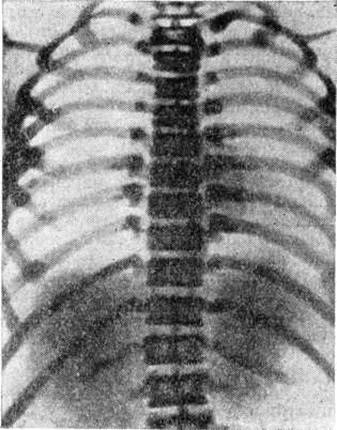

Рентгенологические изменения обнаруживают в костях черепа, таза, в позвонках, проксимальных отделах бедренной кости, рёбрах, реже — в костях верхних конечностей, кистей и стоп. Форма и размеры костей остаются обычно нормальными. В ряде случаев наблюдается нередкое булавовидное утолщение метафизарных отделов длинных трубчатых костей. Структура костей резко изменена. Вместо обычного трабекулярного, сетчатого рисунка кости приобретают гомогенную плотность, причём наибольшая интенсивность компактного костного вещества отмечается в субкортикальных отделах и на границе эпифиза и метафиза, а также по ходу ростковой зоны апофиза (рисунок 3). В результате неравномерного роста скелета поражённые отделы приобретают своеобразный рисунок, образованный параллельно расположенными полосами и полукольцами. В костях черепа в первую очередь поражаются кости, имеющие хрящевое происхождение. Наряду со склерозом костной ткани отмечается сужение каналов, через которые проходят черепные нервы, придаточные пазухи, носа облитерируются. Своеобразный вид приобретают тела позвонков, центральная часть которых просветлена, а по ходу замыкающих пластинок образуются плотные широкие полосы (рисунок 4). Темпы энхондрального окостенения скелета-нередко нарушены, что. проявляется в запаздывании появления ядер окостенения и синостозирования эпифизов в костях кистей и стоп.

Патологический переломы костей чаще всего возникают в подвертельной области бедренной кости, реже в других трубчатых костях и рёбрах. Плоскость перелома, как правило, поперечная или косопоперечная (рисунок 5). Оскольчатые переломы встречаются более редко. Смещение отломков обычно незначительное.